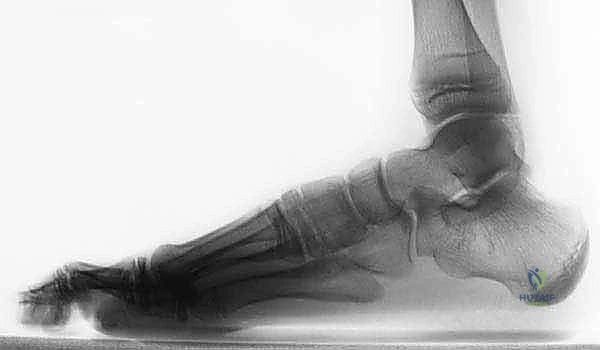

- الأشعة السينية التقليدية (X-Rays): يتم أخذ صور بوضعيات خاصة (مثل وضعية Harris-Beath) لرؤية المفصل تحت الكاحل. قد تظهر الأشعة السينية الائتلاف العظمي بوضوح، بالإضافة إلى علامات ثانوية مثل "علامة حرف C" (C-sign) التي تدل على تشوه في عظم الكاحل، أو وجود نتوءات عظمية (Osteophytes) تشير إلى بداية خشونة المفاصل المجاورة.

- التصوير المقطعي المحوسب (CT Scan): يُعد المعيار الذهبي (Gold Standard) لتشخيص ائتلاف الكاحل العقبي. يطلب الدكتور هطيف إجراء أشعة مقطعية ثلاثية الأبعاد، حيث توفر صوراً متناهية الدقة للتركيب العظمي، تحدد حجم الائتلاف، موقعه الدقيق، ونسبة إصابة المفصل. هذه الخطوة حاسمة جداً قبل اتخاذ قرار الجراحة.

- التصوير بالرنين المغناطيسي (MRI): يتم اللجوء إليه إذا كان الائتلاف غضروفياً أو ليفياً ولم يظهر بوضوح في الأشعة المقطعية، كما يفيد في تقييم حالة الأوتار والأربطة المحيطة، وتحديد مدى التورم في نخاع العظم (Bone Marrow Edema) الناجم عن الإجهاد الميكانيكي.